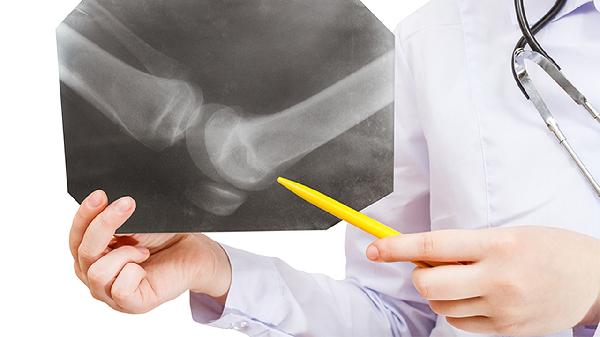

经舟骨月骨周围脱位指月骨脱位合并舟骨骨折,属于复杂性损伤。患者腕关节呈"银叉样"畸形,活动时伴弹响。MRI可评估舟骨血供及韧带完整性。治疗需优先稳定舟骨,采用Herbert螺钉固定骨折,同时处理月骨脱位,术后需长期康复训练恢复腕部功能。

经桡骨茎突月骨周围脱位常伴随桡骨茎突骨折,损伤机制为轴向暴力合并旋转应力。查体可见桡骨茎突压痛及腕关节不稳定。三维CT重建有助于判断骨折块移位程度。治疗需手术复位桡骨茎突骨折块并用微型钢板固定,同时修复月骨周围韧带结构。